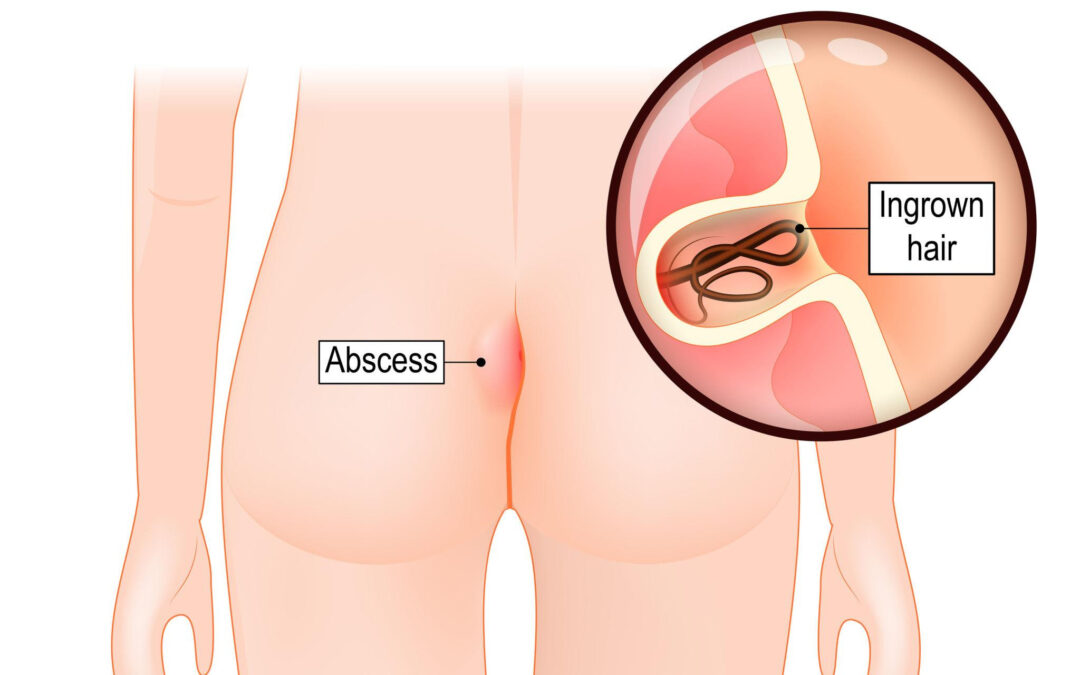

QUISTE PILONIDAL El Quiste pilonidal es una lesión inflamatoria que aparece con mayor frecuencia en la región sacrococcígea, es decir, en el pliegue entre los glúteos cerca del coxis. ¿POR QUÉ OCURRE? Generalmente se produce por: Vellos encarnados Fricción y...